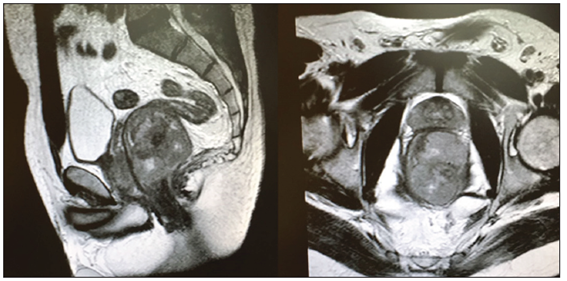

Al no poder demostrarse la afectación de tejidos y órganos vecinos, se decidió practicar una resonancia magnética (RM) pélvica (figura 2), la cual no mostró una clara infiltración de la grasa mesorrectal, aunque sí un borramiento en el lado izquierdo del recto, sugerente de tumoración de tipo GIST.